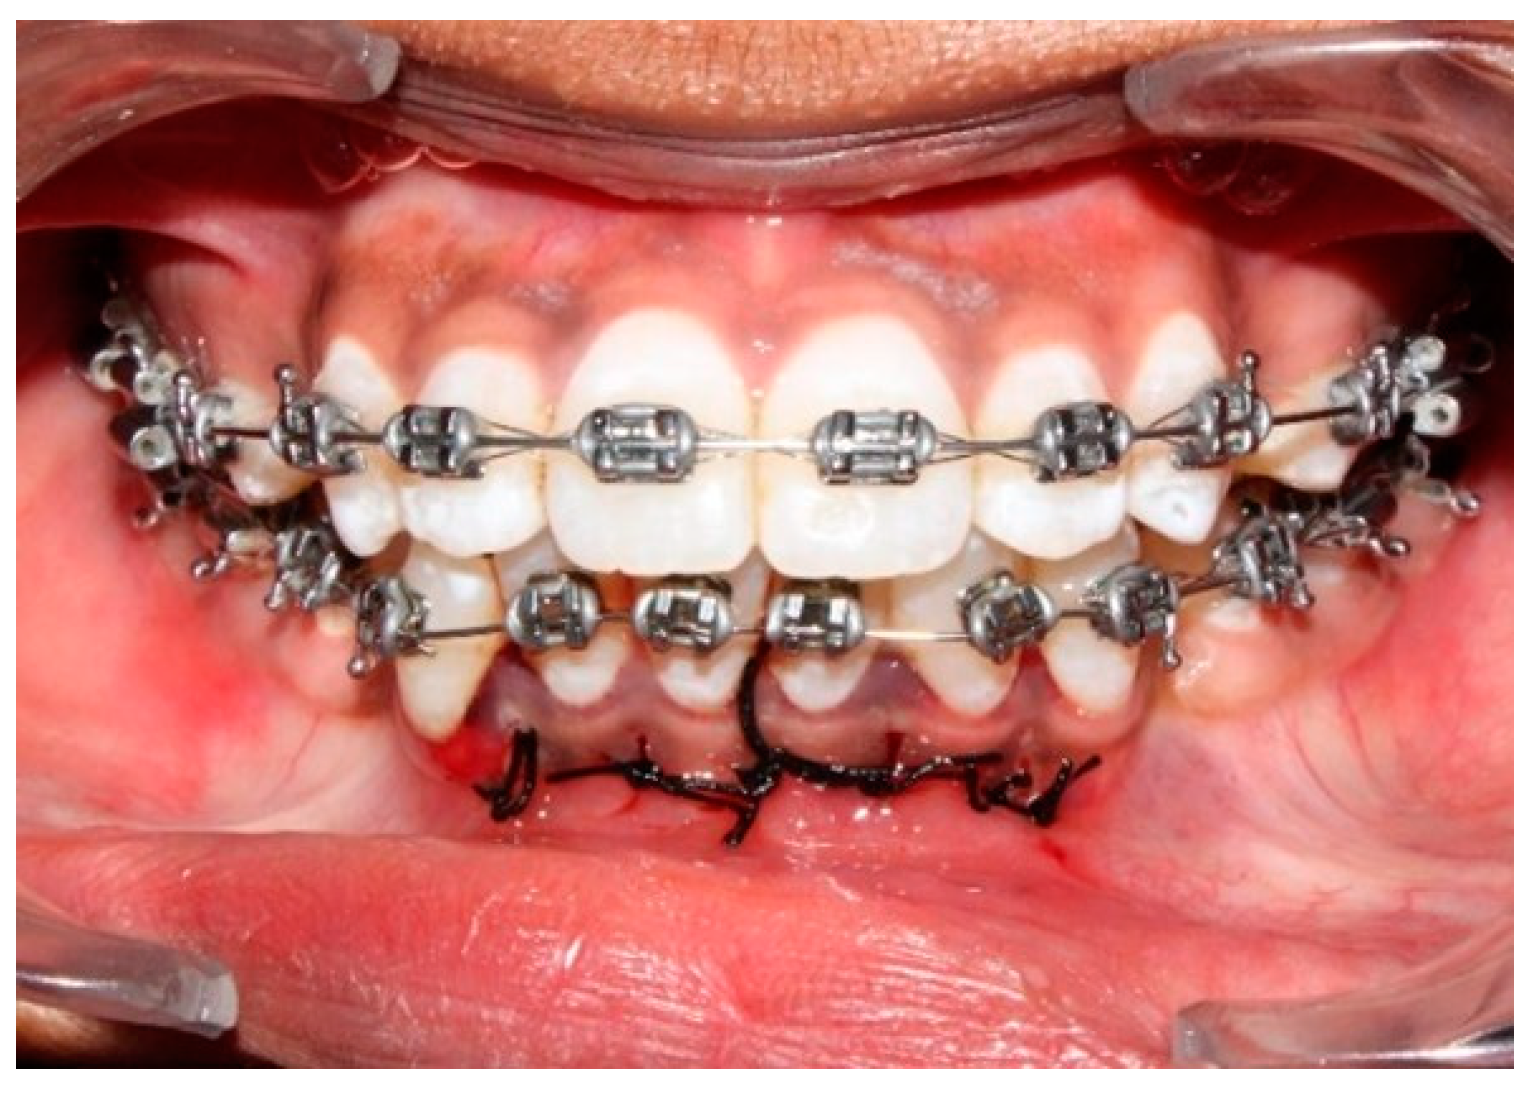

2.3.2. Micro-Osteoperforation Procedure (MOP)